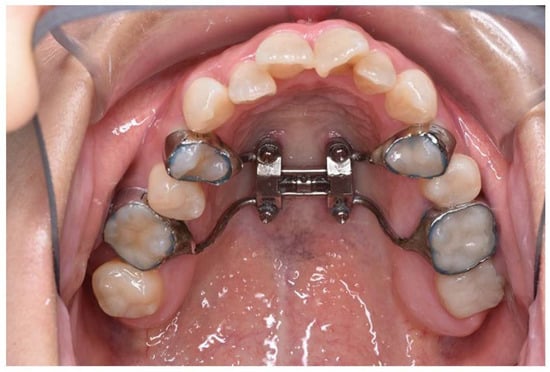

The MARPE device (M.S.E., Maxillary Skeletal Expander, Forest-One Co., cChiba, Japan) was placed by the orthodontist. It was fabricated with orthodontic bands on the first premolars and first molars and designed with four holes for orthodontic screws. The expansion appliance was secured using 11 mm long screws inserted into the bicortical plates of the maxillary bone near the midpalatal suture (Figure 2). Subsequently, orthodontic treatment was initiated, and the patient also began maxillary expansion.

Figure 2. Intraoral view of patient with miniscrew-assisted rapid palatal expansion (MARPE) appliance in place.